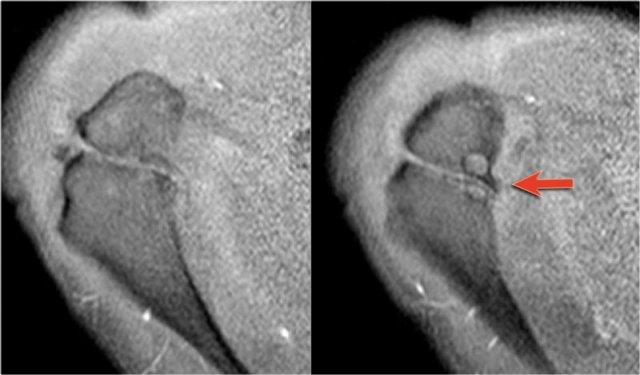

Os Acromiale

Sự thất bại trong quá trình hợp nhất của một trong các trung tâm cốt hóa mỏm cùng vai sẽ dẫn đến hình thành os acromiale.

Tình trạng này xuất hiện ở 5% dân số.

Thông thường đây là phát hiện tình cờ và được xem là một biến thể giải phẫu bình thường.

Os acromiale có thể gây hội chứng chèn ép (impingement) do nếu không ổn định, nó có thể bị kéo xuống dưới trong quá trình dạng tay bởi cơ delta, vốn bám vào vị trí này.

Trên MRI, os acromiale được quan sát rõ nhất trên các lát cắt ngang (axial) phía trên.

Os acromiale cần được đề cập trong báo cáo, vì ở những bệnh nhân được cân nhắc phẫu thuật giải áp dưới mỏm cùng vai,

việc cắt bỏ phần mỏm cùng vai ở phía xa so với khớp sụn (synchondrosis) có thể làm mất ổn định thêm khớp sụn này và cho phép

os acromiale di động nhiều hơn sau phẫu thuật, từ đó làm nặng thêm hội chứng chèn ép (4).

Các hình ảnh MRI lát cắt ngang cho thấy os acromiale kèm theo các thay đổi thoái hóa, bao gồm nang dưới sụn và gai xương (mũi tên).